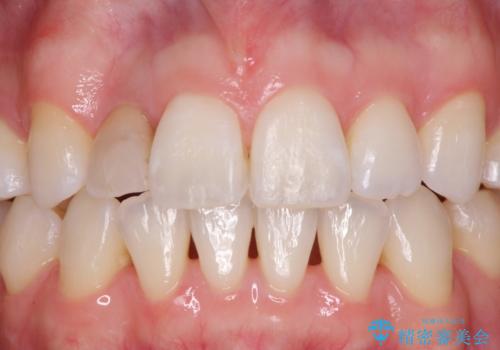

変色した前歯 オーダーメイドタイプのオールセラミッククラウン

- 虫歯により神経を取り除いた前歯の変色が気になるとのことで来院された患者様です。

レントゲン写真より、歯根の炎症が認められなかったため、ファイバーコアによる土台築製後、オーダーメイドタイプのオールセラミッククラウンにて補綴することとしました。

他院で矯正治療をされていたそうですが、矯正治療前から変色は気になっており、歯並びが整ってからは、より気になるようになっていたそうです。

自然に仕上がり、患者様には大変満足していただきました。